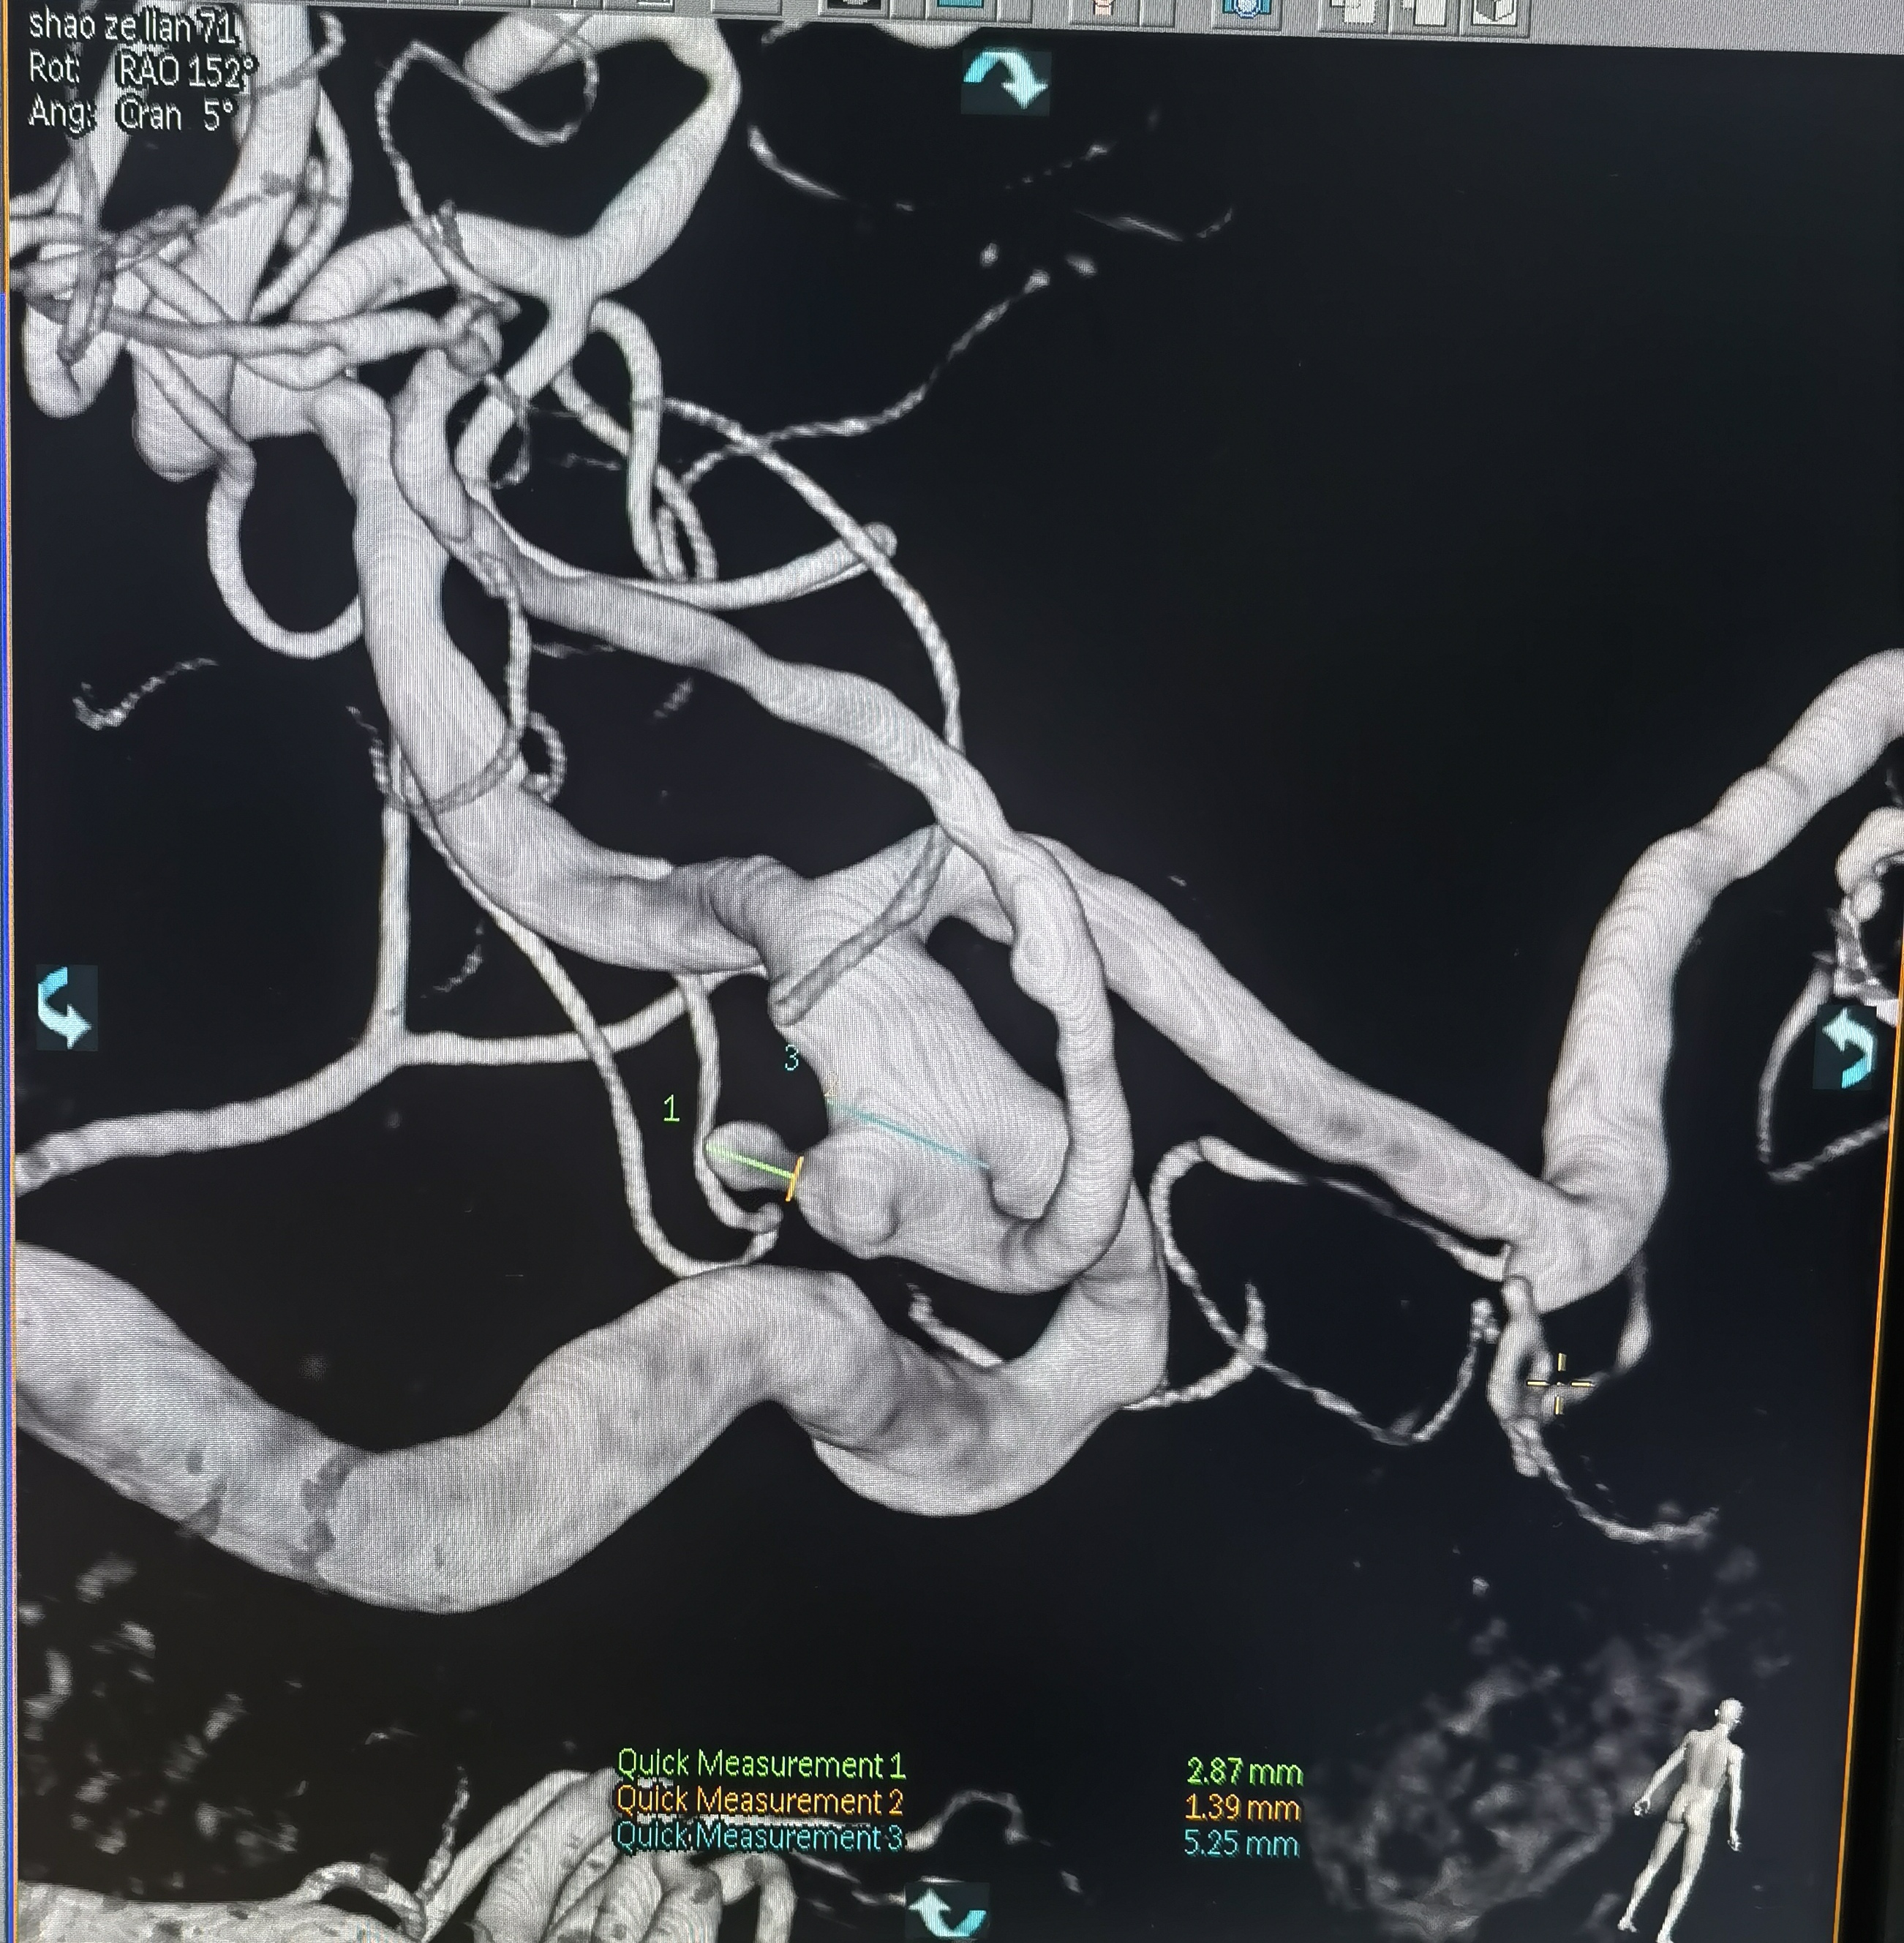

你的浏览器不支持video标签. 入院CT 血管迂曲你的浏览器不支持video标签. RCCA正位,胚胎型大脑后动脉,右侧大脑前动脉纤细。你的浏览器不支持video标签. RCCA3D造影你的浏览器不支持video标签. 右侧3D 右侧后交通动脉瘤形状亦不规则,拟二期治疗。你的浏览器不支持video标签. LCCA正位,胚胎型大脑后动脉,左侧A1供应双侧大脑前动脉。你的浏览器不支持video标签. LCCA3D造影你的浏览器不支持video标签. 左侧3D你的浏览器不支持video标签. 左椎正位,PICA以远未显影。 左侧后交通动脉瘤形状不规则,见子瘤。 拟支架辅助栓塞左侧后交通动脉瘤。 工作位路图,显示子瘤。 微导管首先超选子瘤填塞弹簧圈后,弹簧圈从子瘤脱出,遂应用支架于颈内动脉交通段释放辅助栓塞。你的浏览器不支持video标签. 术中造影你的浏览器不支持video标签. 术中造影你的浏览器不支持video标签. 术中造影你的浏览器不支持video标签. 释放支架,术中造影。你的浏览器不支持video标签. 术后造影你的浏览器不支持video标签. 术后正位你的浏览器不支持video标签. 术后侧位